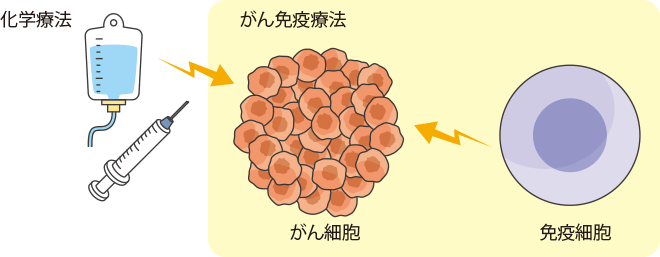

がん細胞を退治しようとする免疫の働き

身わたしたちの身体には、体内に入り込んだ異物(自分の体の細胞ではないもの)を攻撃し、排除して体を守る「免疫」という働きが備わっています。

身体の中でがん細胞ができると、免疫の働きがそれを異物ととらえ、排除しようとします。

しかし、がん細胞は、免疫の攻撃から逃れるために、免疫細胞(T細胞など)にブレーキをかける力をもっています。このように、がん細胞によって免疫にブレーキがかけられた状態や、もともと免疫の働きが弱まった状態などでは、がん細胞を排除しきれないことがあります。

最近では、こうしたがんに関連する遺伝子や免疫の状態を詳しく調べ、治療に役立てる研究が進められています。